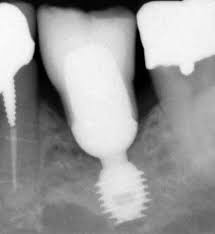

The company that sells this implant

Who is Bicon?